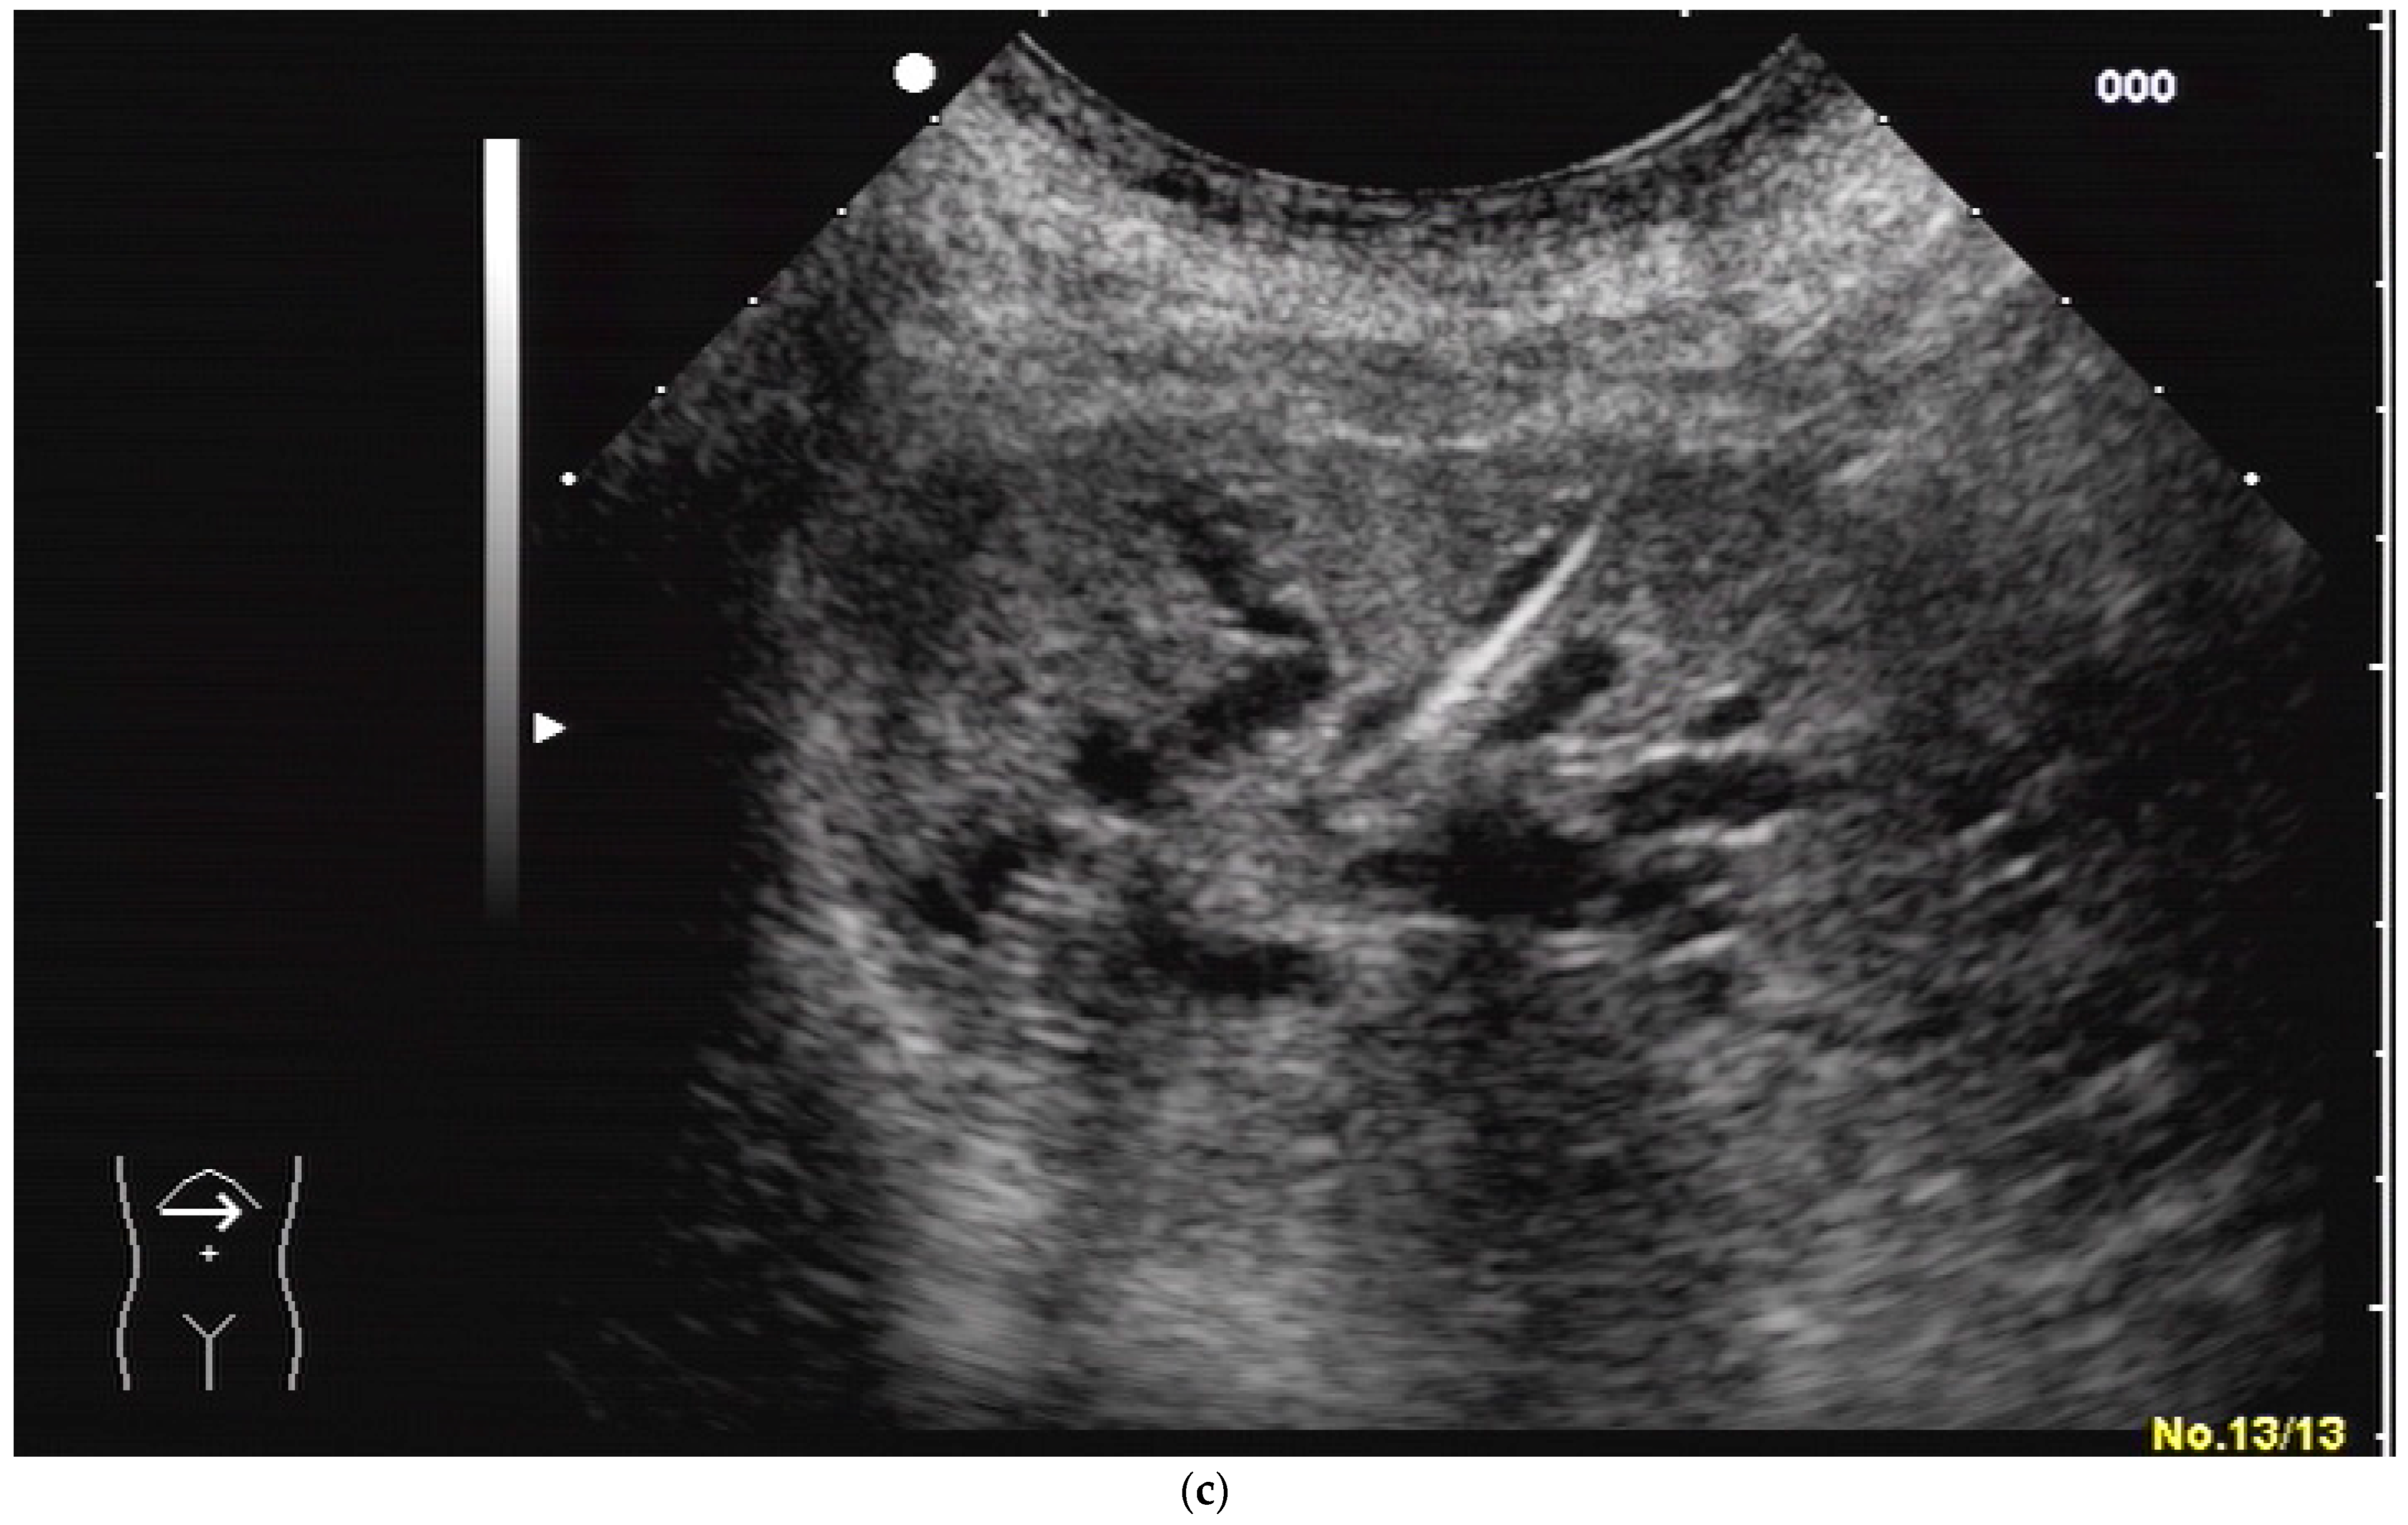

(a) A pointed angle between the needle trajectory and a bile duct of Segment V/VI is given; (b) Puncture of a dilated bile duct in Segment IV at a suitable angle. A guide wire with a bended tip should be used to facilitate the correct advancement; (c) A guide wire is placed in a dilated intrahepatic bile duct in Segment III.

If peripheral bile ducts are not dilated and puncture is difficult, sometimes, targeting the central bile ducts and even the common bile duct close to the hilum are the only options to place drainage. When trying to puncture the common bile duct, it is sensible to enter it as proximal as possible to avoid biliary leakage after drain removal. The needle tract should point towards the distal common bile duct (CBD) to facilitate guide-wire advancement (Figure 5).

Figure 5.

Puncture of the CBD in a patient with pancreatic carcinoma. The tip of the needle is seen in the dilated CBD. Pigtail drainage was placed in the CBD, and ten days later, internal drainage by a self-expanding metal stent was placed using a rendezvous technique (percutaneous transpapillary guide-wire advancement and endoscopic stent placement over the wire).